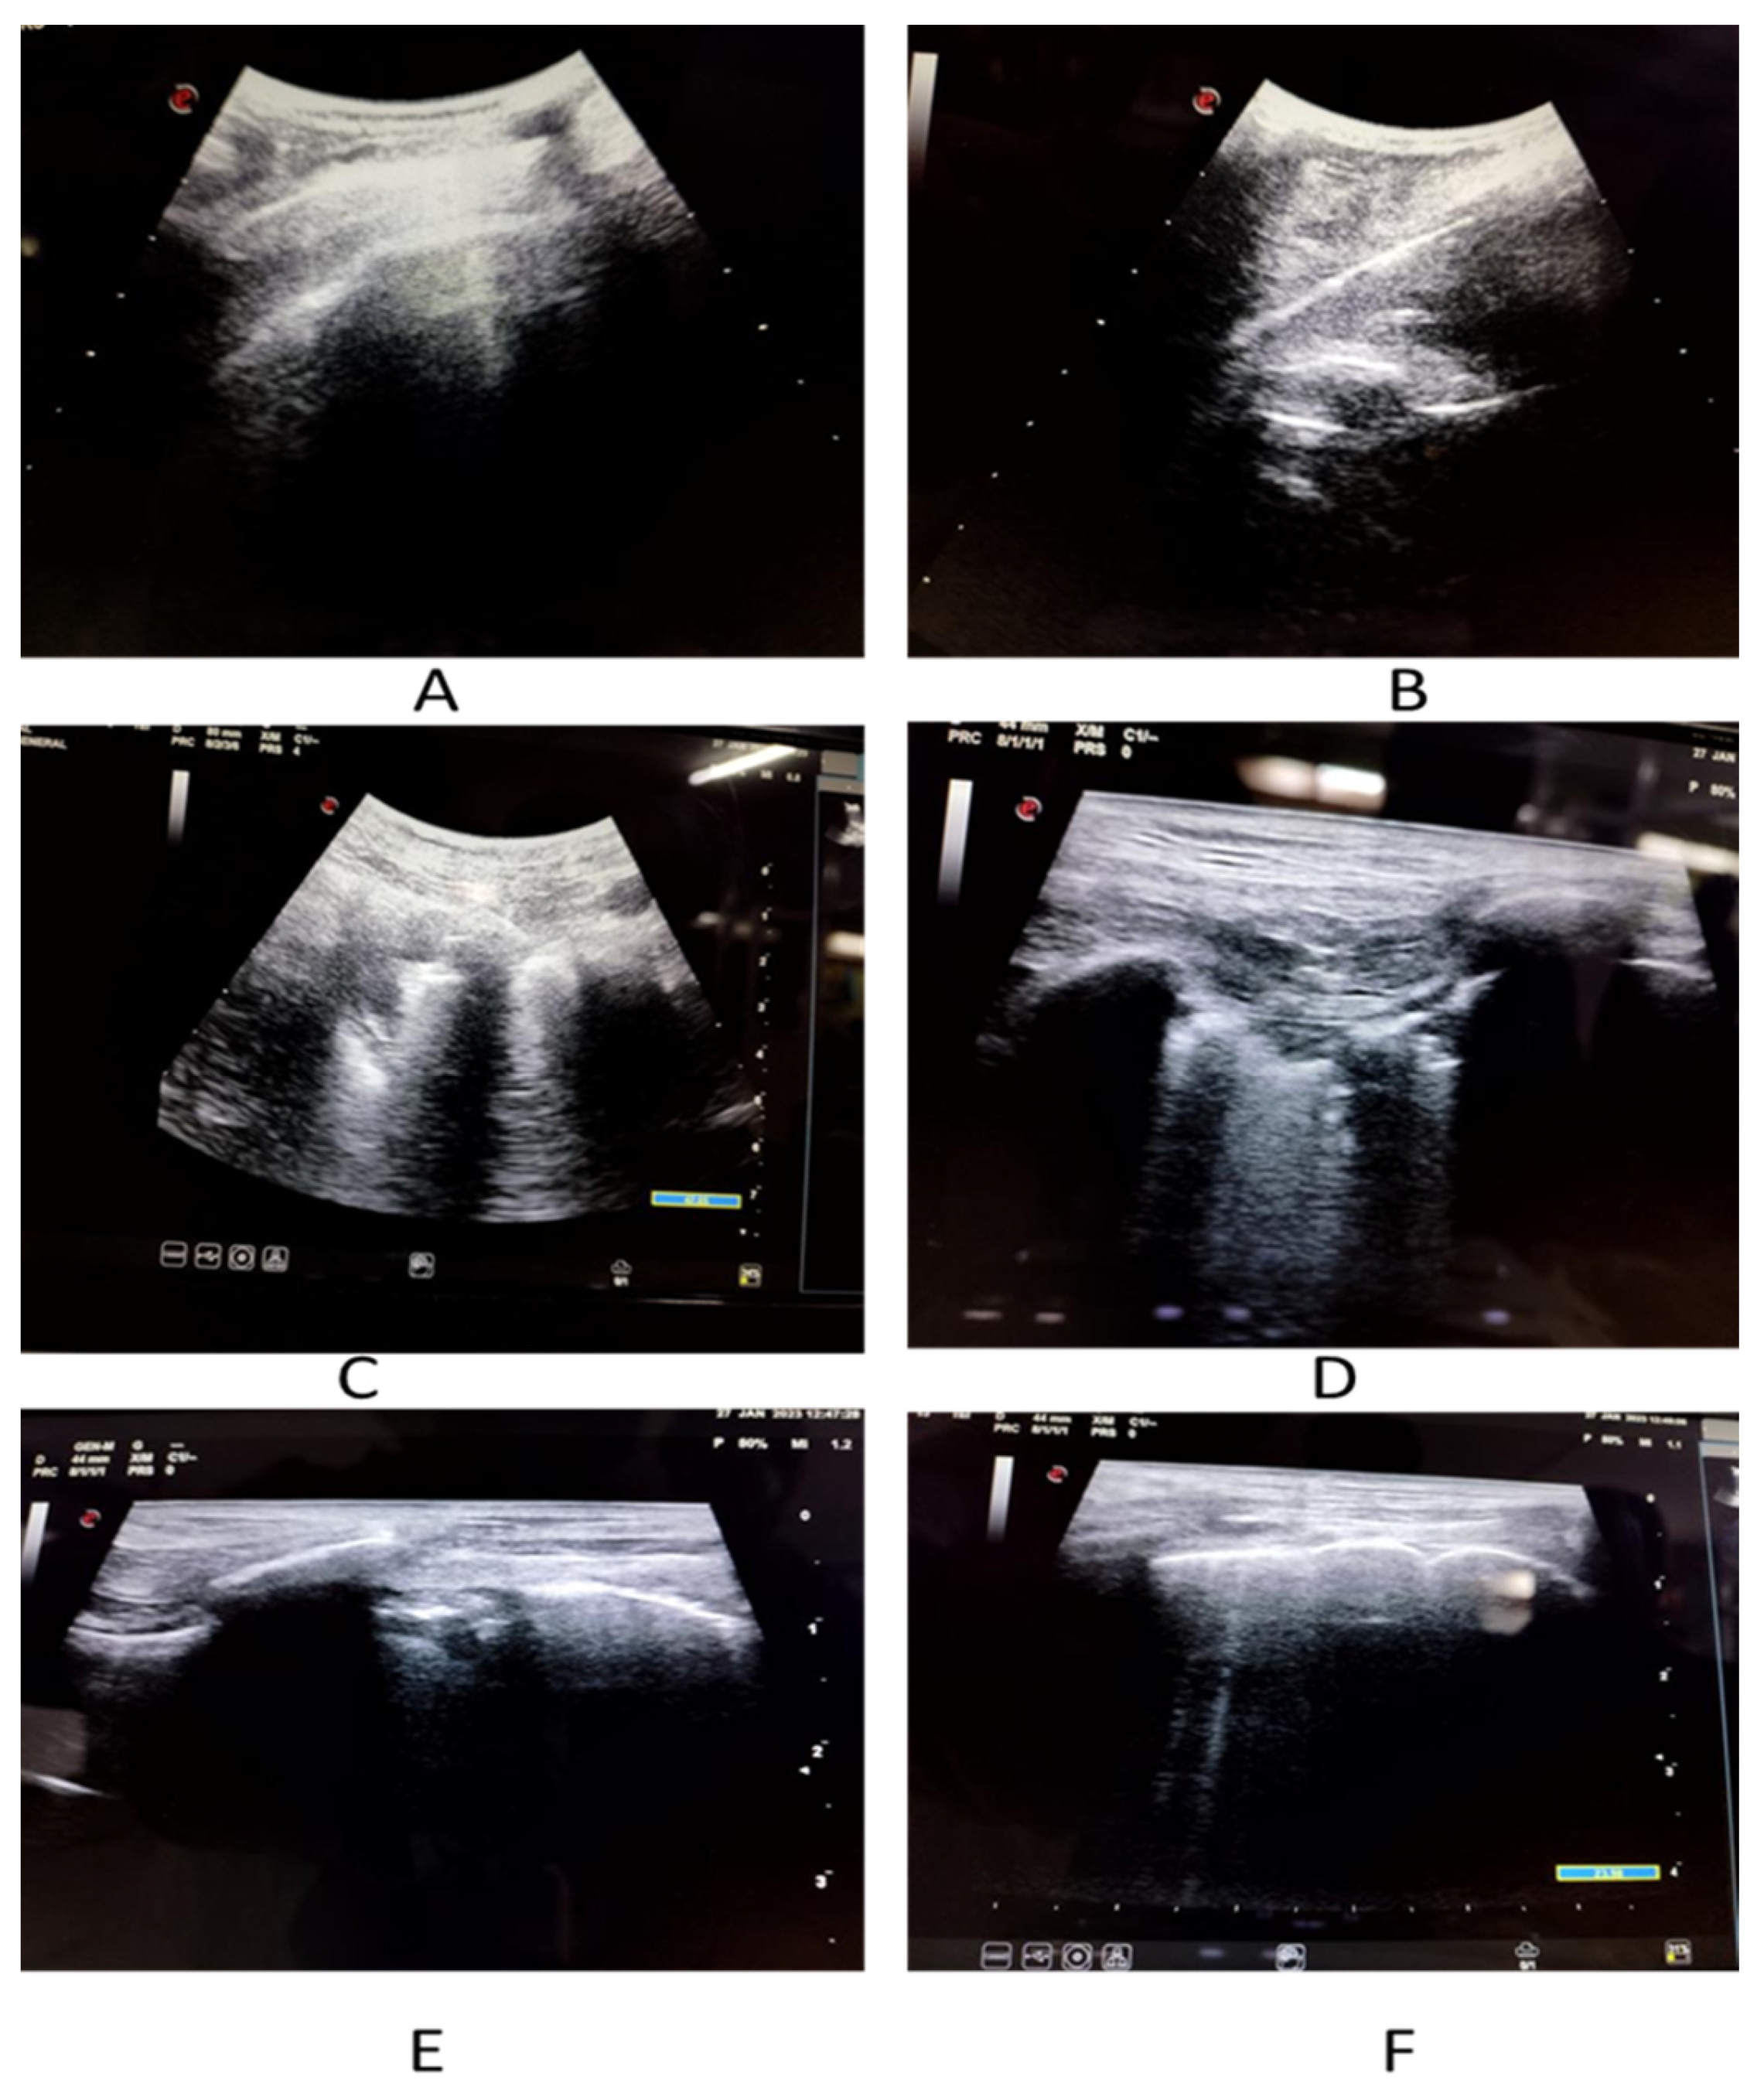

| Lung ultrasonography (n = 152) | |||

| COVID-19 suggestive | 120 (78.95) | ||

| Right pleural effusion | 24 (15.79) | ||

| Left pleural effusion | 21 (13.82) | ||

| Pericardial effusion | 39 (25.66) | ||

| Lung score, (Mean ± SD) | 11.6 ± 4.3 | ||